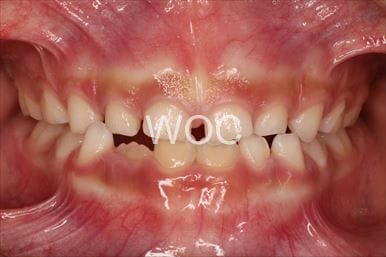

治療前1

治療前2

治療前3

治療前4

治療前5

- 年齢:10歳8ヶ月

- 主訴:出っ歯、ガタガタ

- 診断名:過蓋咬合、叢生、上顎前突

- 装置:可撤式拡大装置、機能的矯正装置

- 期間:2年7ヶ月 ※

- 費用:基本矯正料金:390,000円